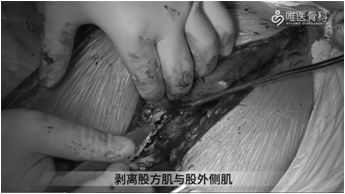

切除瘢痕组织:削薄并切除假体周围多余的瘢痕组织,常规行髋关节后脱位,并给予剥离股方肌与股外侧肌,去除围绕在假体与骨周围的瘢痕。